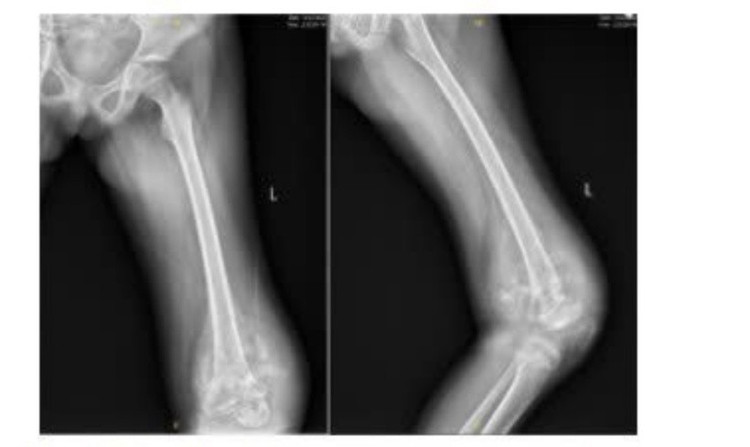

Bệnh nhi K.P.M., 10 tuổi, quê tại Điện Biên, người dân tộc Hà Nhì, nhập viện trong tình trạng sưng đau vùng đùi trái kéo dài, đi lại khó khăn. Qua thăm khám lâm sàng và thực hiện các xét nghiệm hình ảnh học, kết quả MRI cho thấy bệnh nhi M. có khối tổn thương kích thước 12x9cm ở đầu dưới xương đùi, ăn mòn vỏ xương, phá vỡ màng xương và lan vào phần mềm. Kết quả sinh thiết xác định bệnh nhi mắc osteosarcoma đầu dưới xương đùi trái– một thể ung thư xương ác tính thường gặp ở lứa tuổi thiếu niên.

Hình ảnh X Quang lúc bệnh nhi mới nhập viện. Ảnh: BVCC